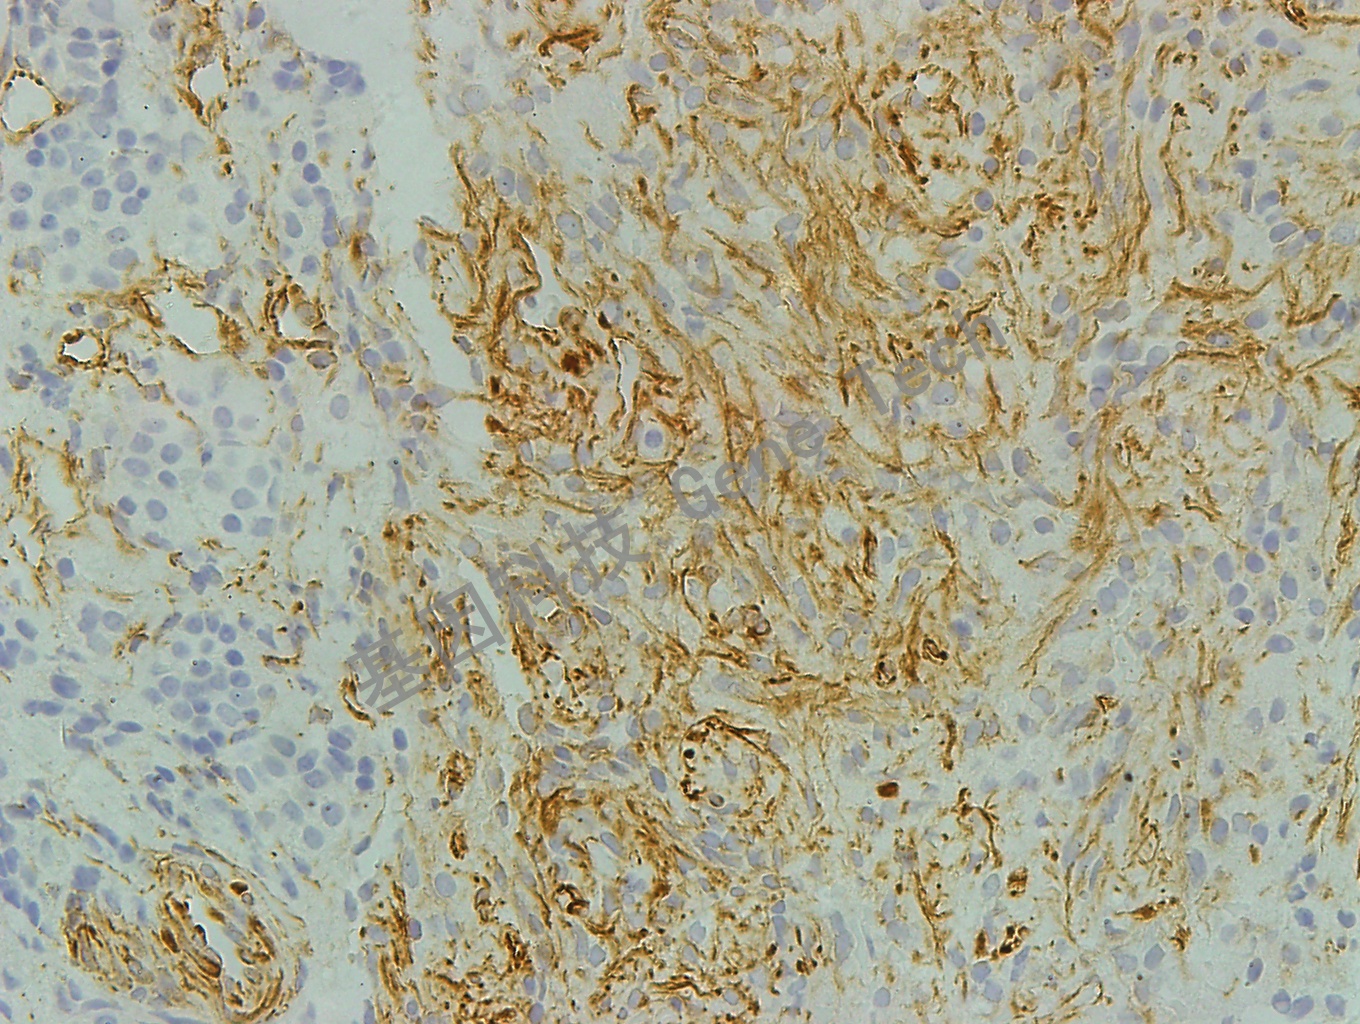

垂体腺瘤石蜡切片,用 Nestin(GT2198)染色,细胞浆阳性,DAB 显色。(10×)

垂体腺瘤石蜡切片,用 Nestin(GT2198)染色,细胞浆阳性,DAB 显色。(40×)

垂体瘤石蜡切片,用 Nestin(GT2198)染色,细胞浆阳性,DAB 显色。(40×)